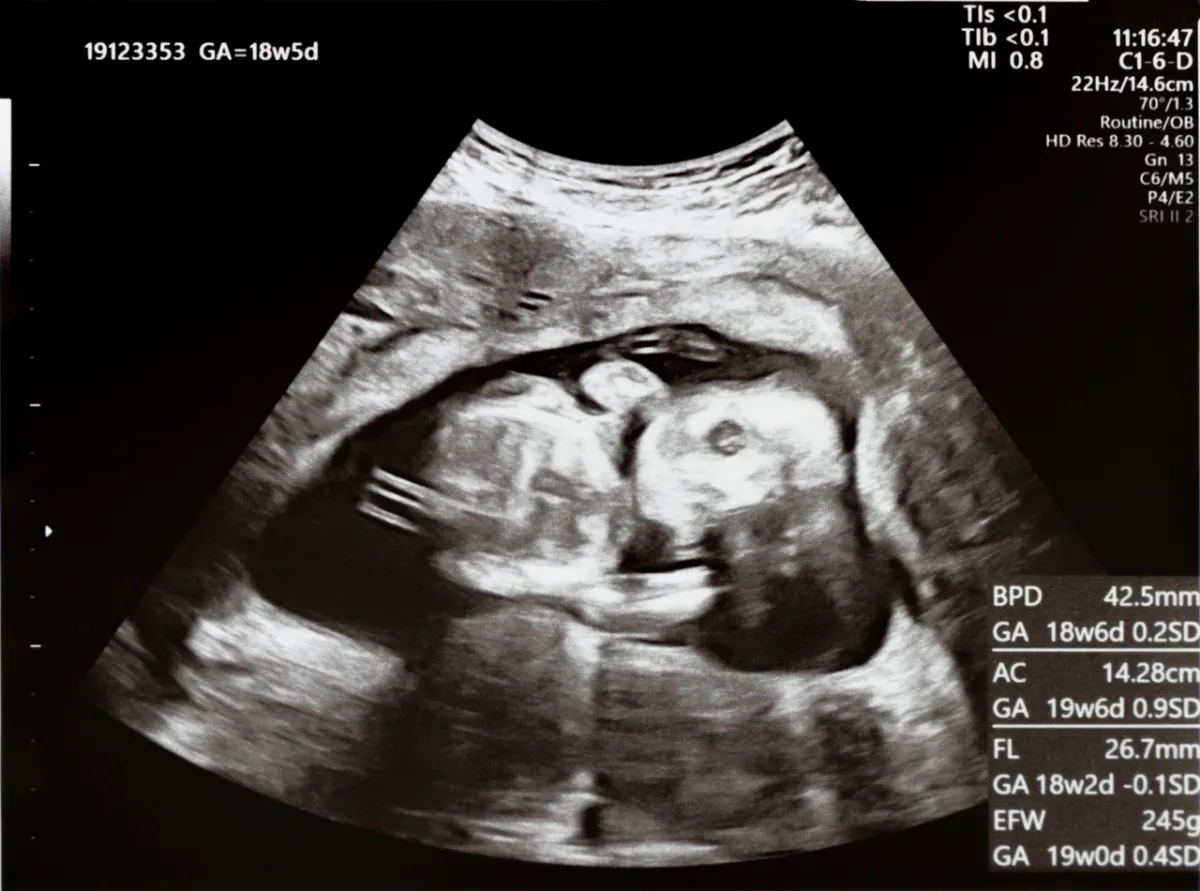

إلى أين وصل نمو طفلي البالغ من العمر 7 أشهر في الرحم؟

1 - في الشهر السابع من الحمل ، تبدأ رئتا طفلك في إنتاج المواد الخافضة للتوتر السطحي وهي مادة تسمح للرئتين بالتمدد والتقلص بشكل صحيح.

2 - يمكن لطفلك أخيرًا فتح وإغلاق عينيه. يمكنه أيضًا الشعور بالتغيرات في الضوء والظلام وقد يتحرك أو يركل عند تعرضه للأضواء الساطعة.

3 - أيضًا، ستبدأ خلايا جلد طفلك في إنتاج الميلانين للمساعدة في إعطاء بشرته لونها.

4 - تتصلب عظام طفلك باستثناء الجمجمة. التي تظل ناعمة حتى الولادة حتى يتمكن طفلك من المرور عبر قناة الولادة بسهولة.

5 - يبلغ نمو دماغ طفلك ذروته - لذا فقد يكون أكثر حساسية تجاه الموسيقى والضوء والشم. إذ يمكنه الآن سماع الأصوات بشكل أكثر وضوحًا، لذا فهو أفضل وقت للقراءة أو الغناء أو التحدث معه.

6 - قد يتغير وضع طفلك في البطن في حوالي الأسبوع 32، وغالبًا ما ينقلب رأسه لأسفل استعدادًا للولادة.